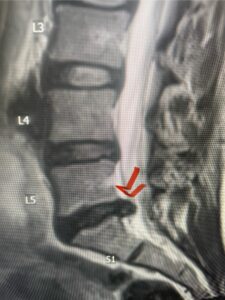

In this next case, this patient is a 47 year-old female who presents with intractable low back pain with severe pain, numbness, and weakness in the right lower extremity that had gotten progressively worse over a year. The patient had failed conservative management including physical therapy and epidurals. She was noted to have ⅘ weakness of plantar flexion. MRI demonstrated a large right L5-S1 disc herniation with severe compression of the descending right S1 nerve root (Fig 3). It was decided to perform a right L5-S1 hemilaminectomy for removal of the disc fragment and decompress the S1 nerve root. When you expose the disc, one must be certain to release any anterior adhesions to the nerve root in order to prevent a dural tear during retraction of the nerve root. It is also important to make sure during exposure and you finally encounter the dura after removing the ligamentum and fat, to make sure you are looking at the nerve root and not the main trunk of the thecal sac because if you don’t you can avulse or damage the nerve root if you retract the wrong structure.

Fig. 3a: Sagittal and axial T2-weighted lumbar MRI images demonstrating large right L5-S1 disc herniation (red arrows)

Fig. 3b

We found a massive subligamentous herniation which had to be revealed by having your partner retract the freed nerve root with a nerve root retractor and putting slight downward pressure on the more medial and anterior disc space. There is nothing more satisfying when the jelly (disc fragment) of the annulus (donut) comes squirting out and you remove a large chunk of disc material that clearly was stretching the ligament membrane and compressing the nerve root. This does cause back pain in addition to radiculopathy not only by the component of mechanical compression but also the stretching of the nerves within the ligament. We performed this surgery and noted that the nerve root was a very angry red color or hyperemic and we removed a large subligamentous fragment. The patient had improvement of her preoperative radicular symptoms.